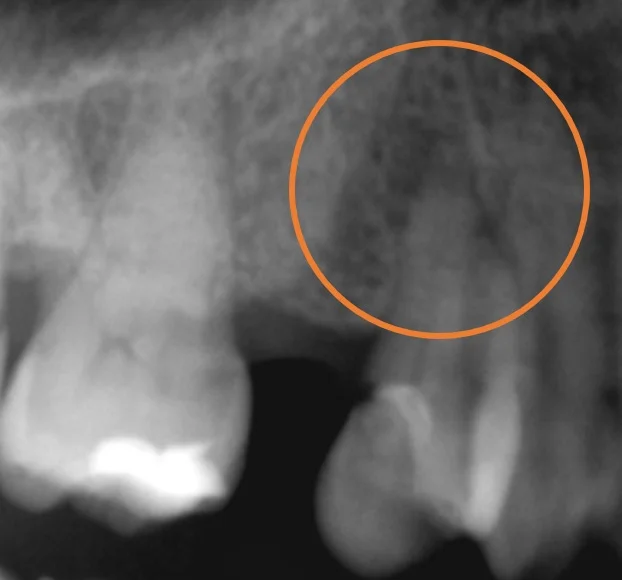

で、中断していたダイレクトボンディングを完了したのがこちら。

こちらの患者さんはステイニングを希望されなかったので、一切着色を使用せずに行いました。

ステイニングを行っていない為、立体感は乏しいですが、パット見た時の違和感はないようにできたと思います。

教科書的には神経の治療を行ったものに関しては、かぶせ物をすることが正しいのですが・・・

歯というものは削れば削るだけ寿命が短くなってしまいます。

そういうことを考えると、根管治療+ダイレクトボンディングは非常に相性の良い治療かと思います。